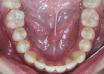

case dot 改善後牙錯咬

case dot 改善前牙錯咬

case dot 排整牙齒

case dot 扶正大臼齒

case dot 拔牙改善嚴重擁擠及中...

case dot 改善齒間縫隙過多